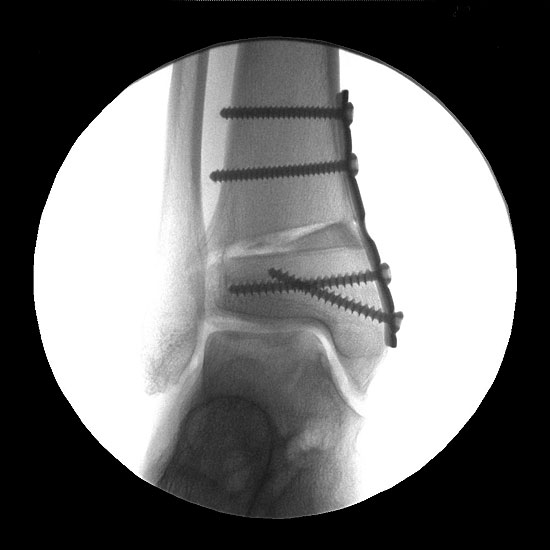

Abbildung 17

Gleichzeitig bestehende Achsdeformitäten oder Instabilitäten sind im Rahmen des Eingriffs ebenfalls zu therapieren. Hierbei können alle Verfahren der Rückfusskorrektur eingesetzt werden. Auch Kapsel-Band-Rekonstruktionen sind nach den Standard-OP Techniken möglich. Abbildung 17 zeigt einen Patienten mit gleichzeitig durchgeführter supramalleolärer Korrekturosteotomie.

Von 42 Patienten mit Knorpeldefekten am Talus (Grad III und IV entsprechend der Klassifikation der International Cartilage Research Society (ICRS), größer 1,5 cm²) liegen Ergebnisse von 24 und mehr Monaten vor. Intraoperativ kam es zu keinen Komplikationen. Bei einem Patienten kam es zu einer postoperativen Wundheilungsstörung. In zwei Fällen war eine Osteotomie des Innenknöchels notwendig, in 31 Fällen wurde eine zusätzliche Spongiosaplastik vom Kalkaneus verwendet. Der AOFAS-Score (Score der American Orthopedic Foot and Ankle Society, basierend auf dem von Kitaoka etablierten Score 22 verbesserte sich von 47,3 ± 17,2 auf 87,5 ± 9,7. In 3 Fällen zeigten sich im MRT-Verlauf erneute Zysten. In 4 Fällen wurde bei Restbeschwerden eine erneute Arthroskopie durchgeführt. Dabei zeigte sich bei zwei Fällen ein instabiles Transplantat, in den anderen beiden Fällen wurde eine hypertrophe Regeneratbildung mit Impingement festgestellt. Bei einem der Patienten mit erneuter Zystenbildung wurde bei erheblicher Symptomatik eine erneute Rekonstruktion mit Spongiosaplastik vom Beckenkamm durchgeführt. Die restlichen MRT-Verläufe wiesen eine gute Defektfüllung ohne vermehrte Ergussbildung auf (Abbildung 18).